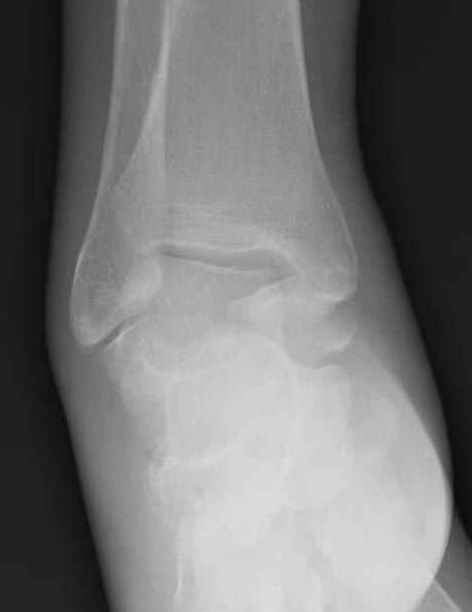

Уважаемые участники русского Ортофорума, поздравляю всех со всеми прошедшими праздниками: Новым годом, Рождеством, Hanukkah, Kwanzaa, желаю участникам всего наилучшего и здоровья.Повреждение таранной кости.Больной 81г автоавария, повреждение таранной кости, здесь снимки. Какие рекомендации?Djoldas Kuldjanov, MDDepartment of Orthopedic SurgerySt. Louis University Medical Center

Вдогонку по поводу перелома таранной кости, больная 81, не страдает диабетом, перелом закрытый, в первый же день поступления ограничились временным наружным фиксатором (как на снимке).

За пару недель насчитал 5 больных с переломом таранной кости, из них двое с двусторонним повреждением.

Из-за отека на стопе тактика лечения у всех была

одинаковая: временная наружная фиксация до спадения отека, при изолированных переломах они выписывались домой и через дней 7 госпитализировались на оперативное лечение.

Примеры на снимке...